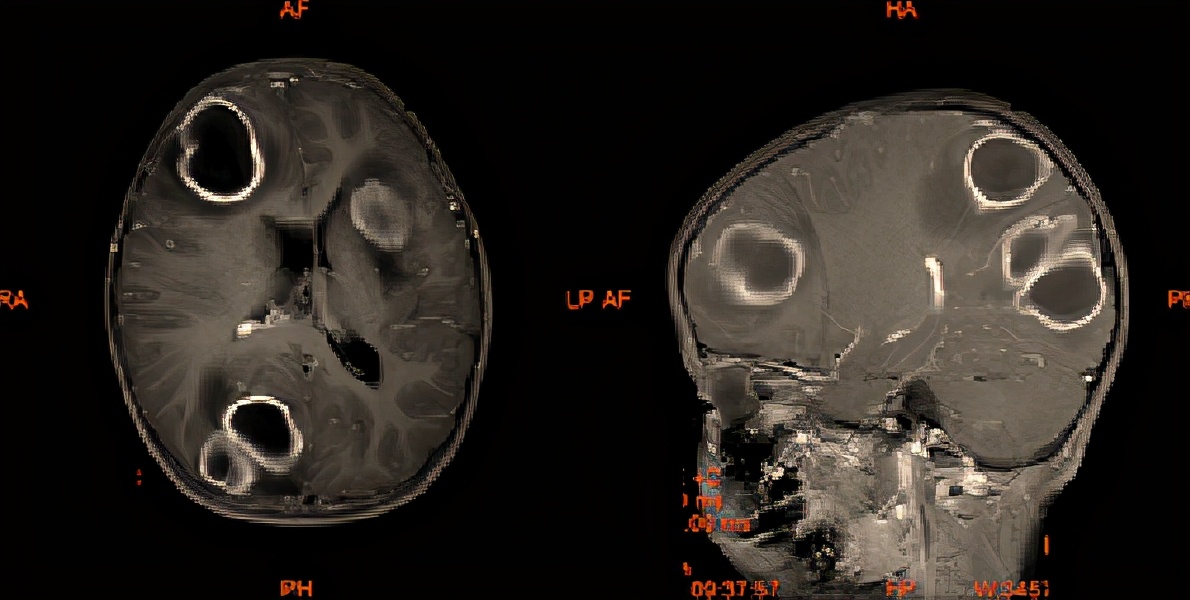

增强磁共振显示颅内多发环形强化病灶

阳阳的妈妈把孩子带到新华医院,住进了儿外神经疾病诊治中心与儿感染科联合病房。入院后,头颅MRI检查发现,阳阳的颅内竟有好多个病灶,大的如鸡蛋大小。面对复杂的病情,新华医院儿外神经疾病诊治中心陈若平主任、儿感染科黄丽素主任成立了联合诊治小组,经儿外神经疾病诊治中心、儿感染科、儿急危重症医学科、影像科、检验科微生物室的讨论,确定阳阳颅内占位是多发脑脓肿。

果不其然,后面的头颅MRI随访也印证了这一推测。磁共振上阳阳脑内的脓肿越来越小,可以改成口服抗生素治疗了,经58天治疗,阳阳终于出院了。

春节期间,阳阳来新华医院复诊,头颅MRI显示脓肿吸收良好,后期也不需要继续服用抗生素治疗。